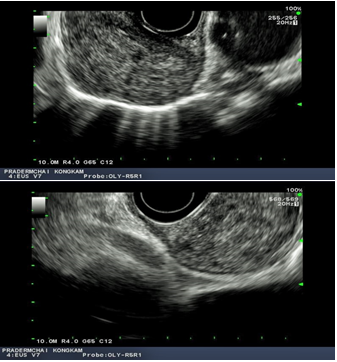

A 59-year-old male who was under surveillance post liver transplant from HCC 4years ago, had elevated alpha fetoprotein (AFP) at 258.3ng/ml and a positron emission tomography–computed tomography (PET-CT) showing an increased uptake lesion of standardized uptake value (SUV) 7.5 at gastro-esophageal junction (Figure 1). Upper endoscopy showed unremarkable esophageal mucosa so EUS was performed showing a homogeneous hypoechoic mass measuring 35x20mm from the 3rd layer of the distal esophageal wall (Figures 2.1 & 2.2) and EUS-FNA was performed. Cytopathology was consistent with metastatic HCC (Figures 3.1 & 3.2). The patient expired 20months later from progressive disease with systematic bacterial infection despite multidisciplinary treatments.

Figure 2a & 2b Endoscopic ultrasound showed a sub-mucosal homogeneous hypo-echoic mass measuring 20x35 mm in diameter, being located at 34-39 cm from incisor. The lesion originated from third layer of esophageal wall as shown in figures.